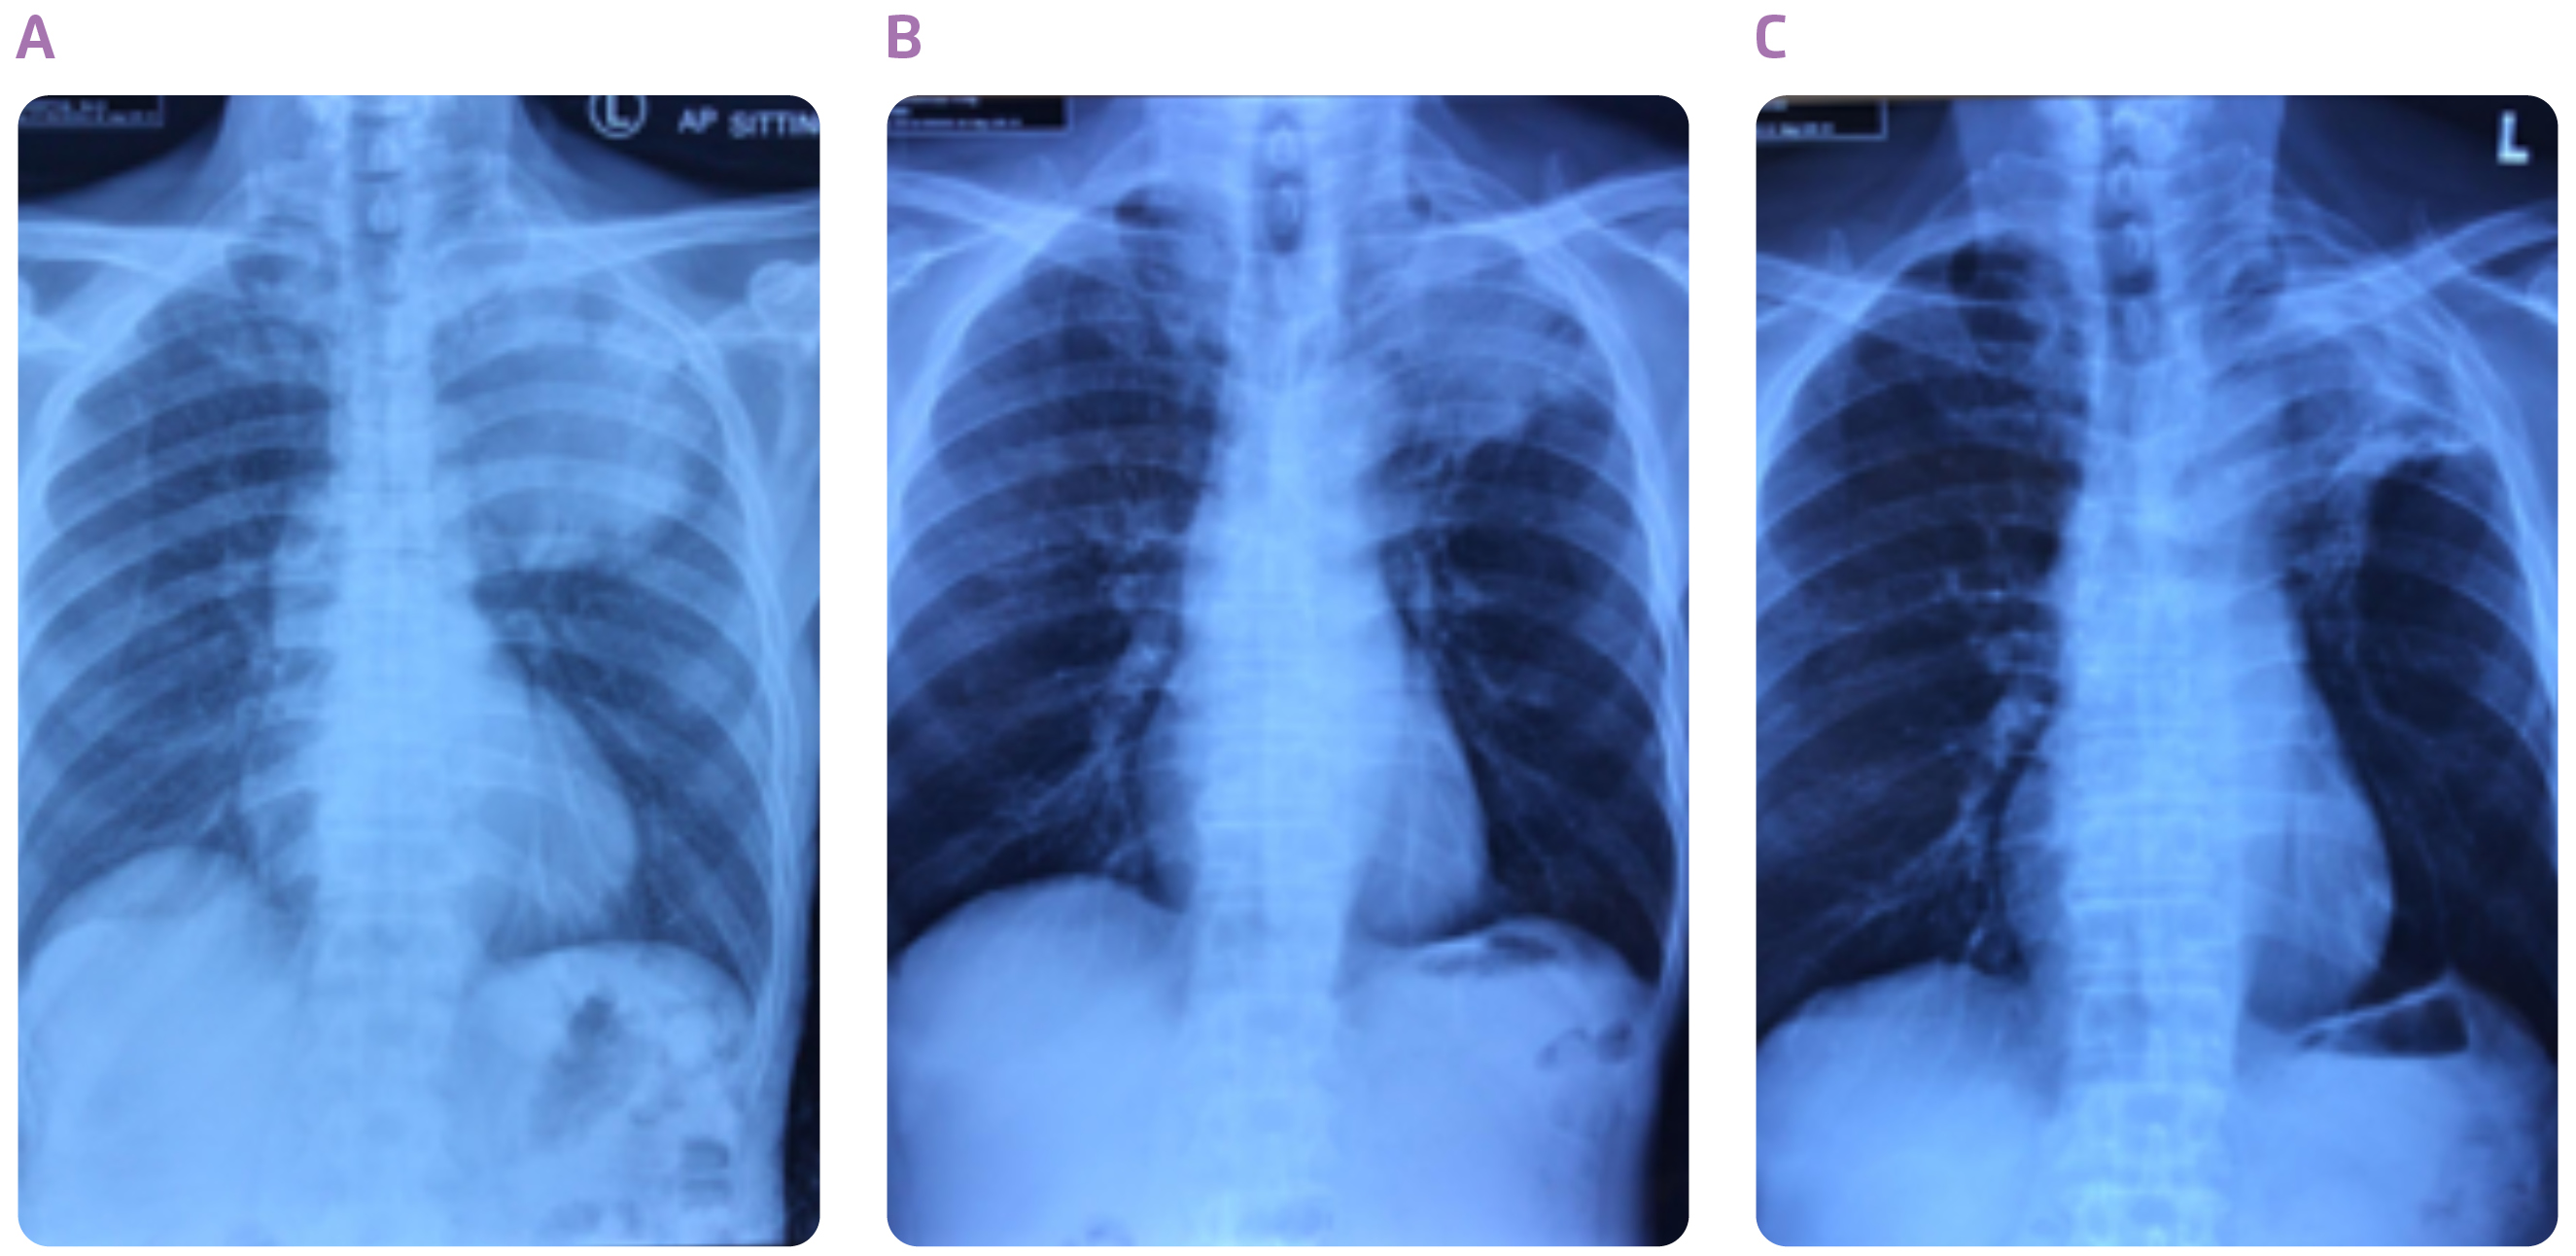

Dr. Choy shared a case of the use of durvalumab consolidation after cCRT in stage III NSCLC. The patient was a 65-year-old construction worker who had smoked a pack a day for 40 years. He was presented with anterior and posterior upper chest wall pain on the left side of his body, which he had experienced for 1 year, and slight shortness of breath. Positron emission tomography-computed tomography (PET-CT) scan of the chest indicated a mass measuring 8.7 cm in diameter in the left upper lobe (Figures 1A and 2A). The tumour had grown into mediastinum, surrounding the aortic arch and descending thoracic aorta. Multiple hypermetabolic lymph nodes were detected. CT-guided biopsy revealed adenocarcinoma. No evidence of distant metastases to the liver, adrenal glands and bones led to a diagnosis of stage IIIB NSCLC (T4N2M0). His serum carcinoembryonic antigen (CEA) level at the time of diagnosis was 143 ng/mL. Molecular profiling revealed the tumour was negative for epidermal growth factor receptor (EGFR) mutation and anaplastic lymphoma kinase (ALK) rearrangement, while the tumour proportion score (TPS) of PD-L1 was 10-20%.

In the light of the fact that the tumour is unresectable, the patient received 7 cycles of weekly carboplatin (area under the plasma concentration time curve [AUC] = 2) and paclitaxol (taxol) (45 mg/m2) in combination with definitive concurrent radiotherapy (66 Gy for 33 fractions). After completion of cCRT, the tumour shrank (Figure 1B), with a slight improvement in chest pain. He attained partial response with the cCRT, and his serum CEA level plummeted to 30.4 ng/mL. Although he experienced dysphagia, and desquamation of anterior and posterior chest wall skin during the treatment, all these adverse events subsided rapidly after the treatment.

The achievement of partial response with the cCRT, led to the choice of durvalumab consolidation treatment. The patient started receiving durvalumab (10 mg/kg) every 2 weeks at 19 days after completion of cCRT. The tumour continued to shrink with the treatment (Figure 1C), and measured 6.3 cm in diameter after the patient had taken 8 doses of durvalumab (Figure 2B). The consolidation treatment was well-tolerated, and the patient only had a mild rash for the first two months. The patient has now completed the 26 doses of durvalumab, and his serum CEA level has further dropped to 2.9 ng/mL. He is able to be fully committed to his work as a construction worker. “Durvalumab consolidation treatment is highly useful in preventing disease progression in patients with unresectable, stage III NSCLC following cCRT,” concluded Dr. Choy.

Figure 1. Chest X-rays taken (A) at diagnosis, (B) after cCRT and (C) after 22 doses of durvalumab